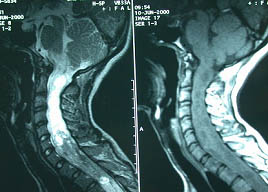

术前术后照片对比